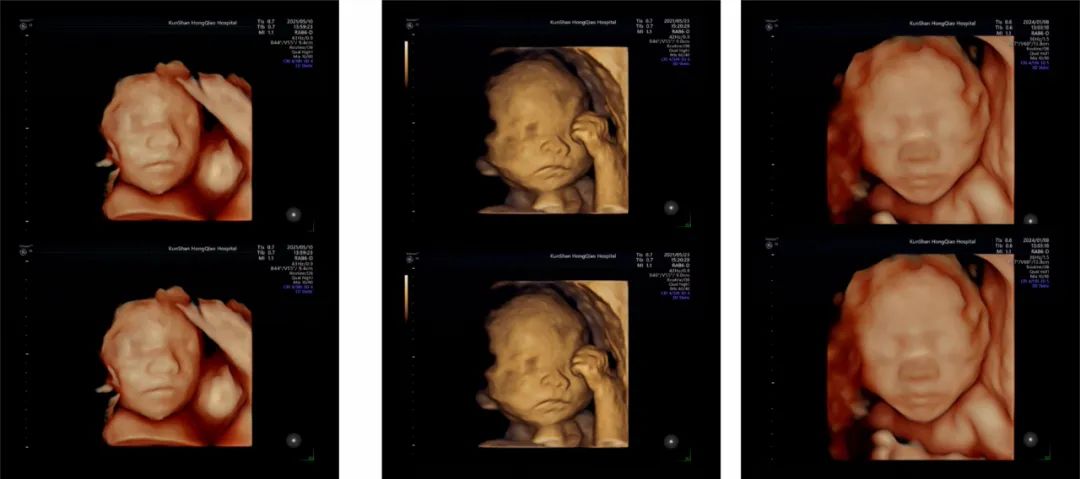

高清四维彩超,与宝宝的鲜活“初见”

医院引进美国GE-E10高端四维彩超设备,为准父母带来清晰、动态的胎儿影像体验,让您直观感受宝贝的每一个可爱瞬间。

鲜活动态影像,清晰看见宝贝:告别传统模糊影像,实时、立体查看宝宝的五官轮廓、表情变化(如打哈欠、吮吸拳头)和灵动姿态(伸懒腰、蹬腿),打造温馨而难忘的“初见”时刻。

安全无创,全程无忧:严格遵循国际安全标准,采用低输出功率超声技术,无痛、无辐射,确保母婴安全与舒适。

专业健康评估:超声团队通过清晰影像,观察胎儿生长发育、活动状态及子宫内环境,为产科医生提供有价值的影像学参考。

定格珍贵记忆:家人可共同见证宝宝实时动态,留存这份独特温馨的生命礼物。